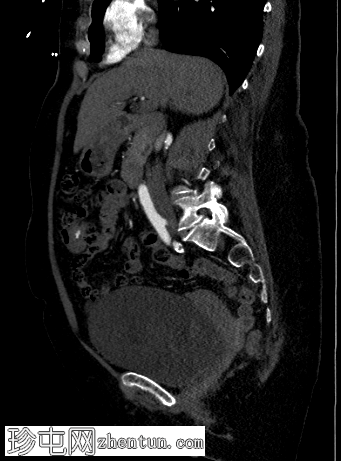

轴位

平扫

弥漫性结肠憩室病,无憩室炎证据。

横结肠中段可见一憩室,动脉期开始出现异常造影剂外渗,门静脉期增多,憩室腔内亦可见造影剂外渗,提示憩室出血伴活动性动脉出血。